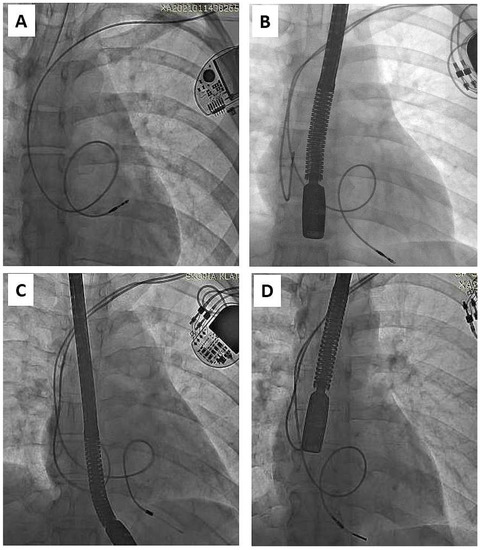

Figure 2.

Another trap of lead extraction in young adults—redundant lead slack (but planned) resulting in strong adherence to the heart structures (examples A–D). It increases the risk of targeted lead fracture, atrial wall rupture or injury to the tricuspid apparatus. Lead slack to allow for growth was supposed to prevent lead straightening, but his technique did not live up to expectations and was abandoned. (A) VVI pacing system. Old unnecessary (but made on purpose) lead loop located in RA and RVOT. (B) DDD pacing system. Proper atrial lead route and loop on ventricular lead finally located in RVOT. (C) DDD pacing system two leads, two loops (D) Another one DDD system. Proper atrial lead course and loop of ventricular lead finally located in RVOT. Presence of old models of passive leads indicates for more difficult extraction.